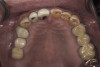

(16.) Preoperative mandibular, occlusal view.

Figure 16